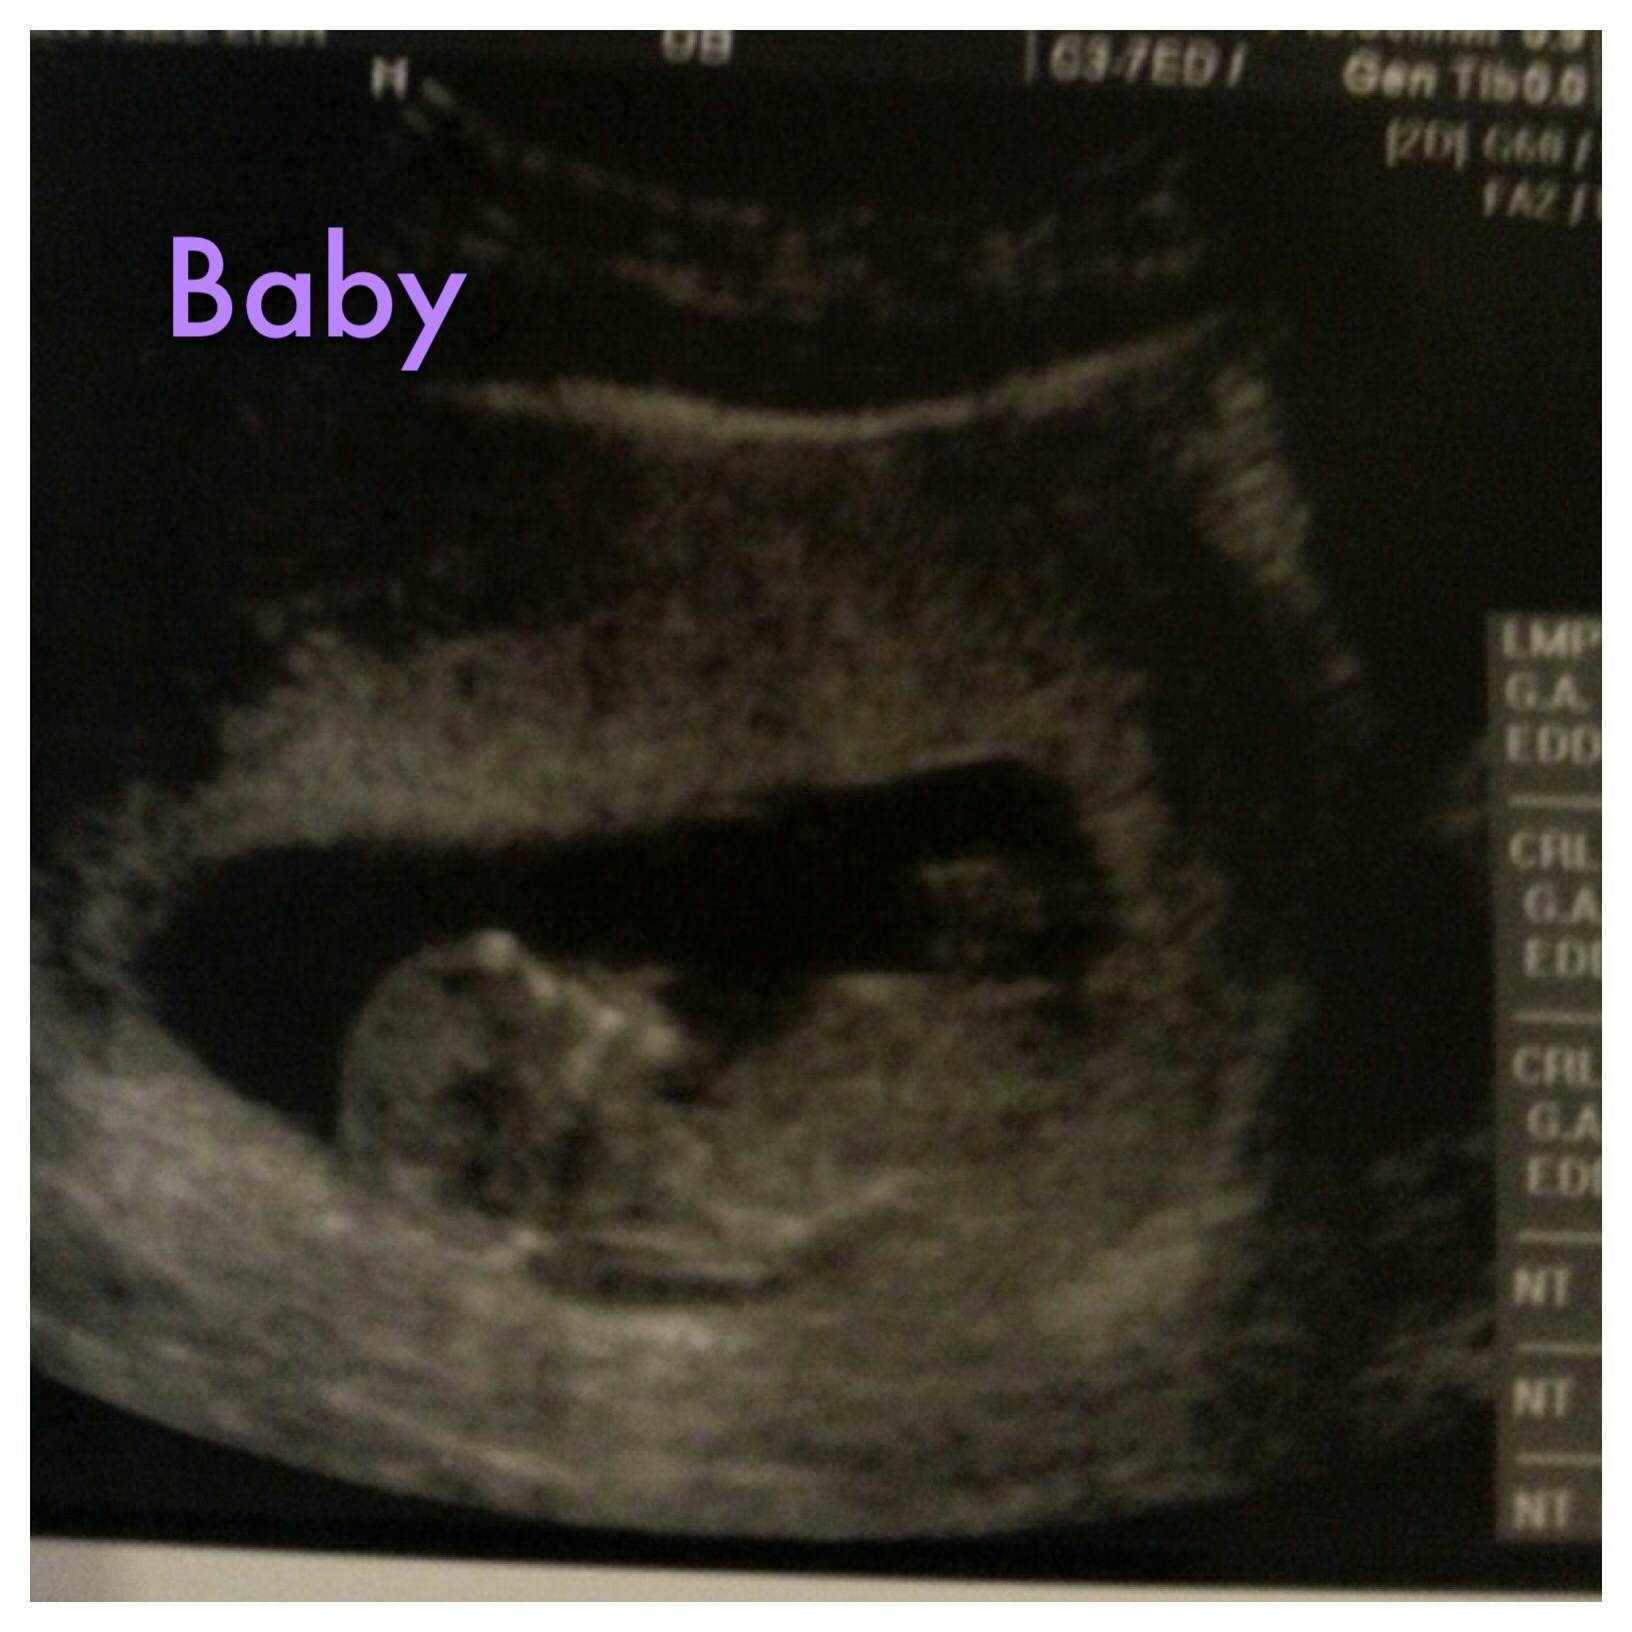

I haven't been on here in ages but can you guess for my BFF? She didn't sway and these are the best pics she has. TIA!!

I'm not great at guessing and I'm not sure what exactly I'm looking at here....but I'm leaning girl.

On the pic it looks like baby is measuring 11 w 6 days - if so I think it might be too early to guess. Nub looks flat, but it might still rise.